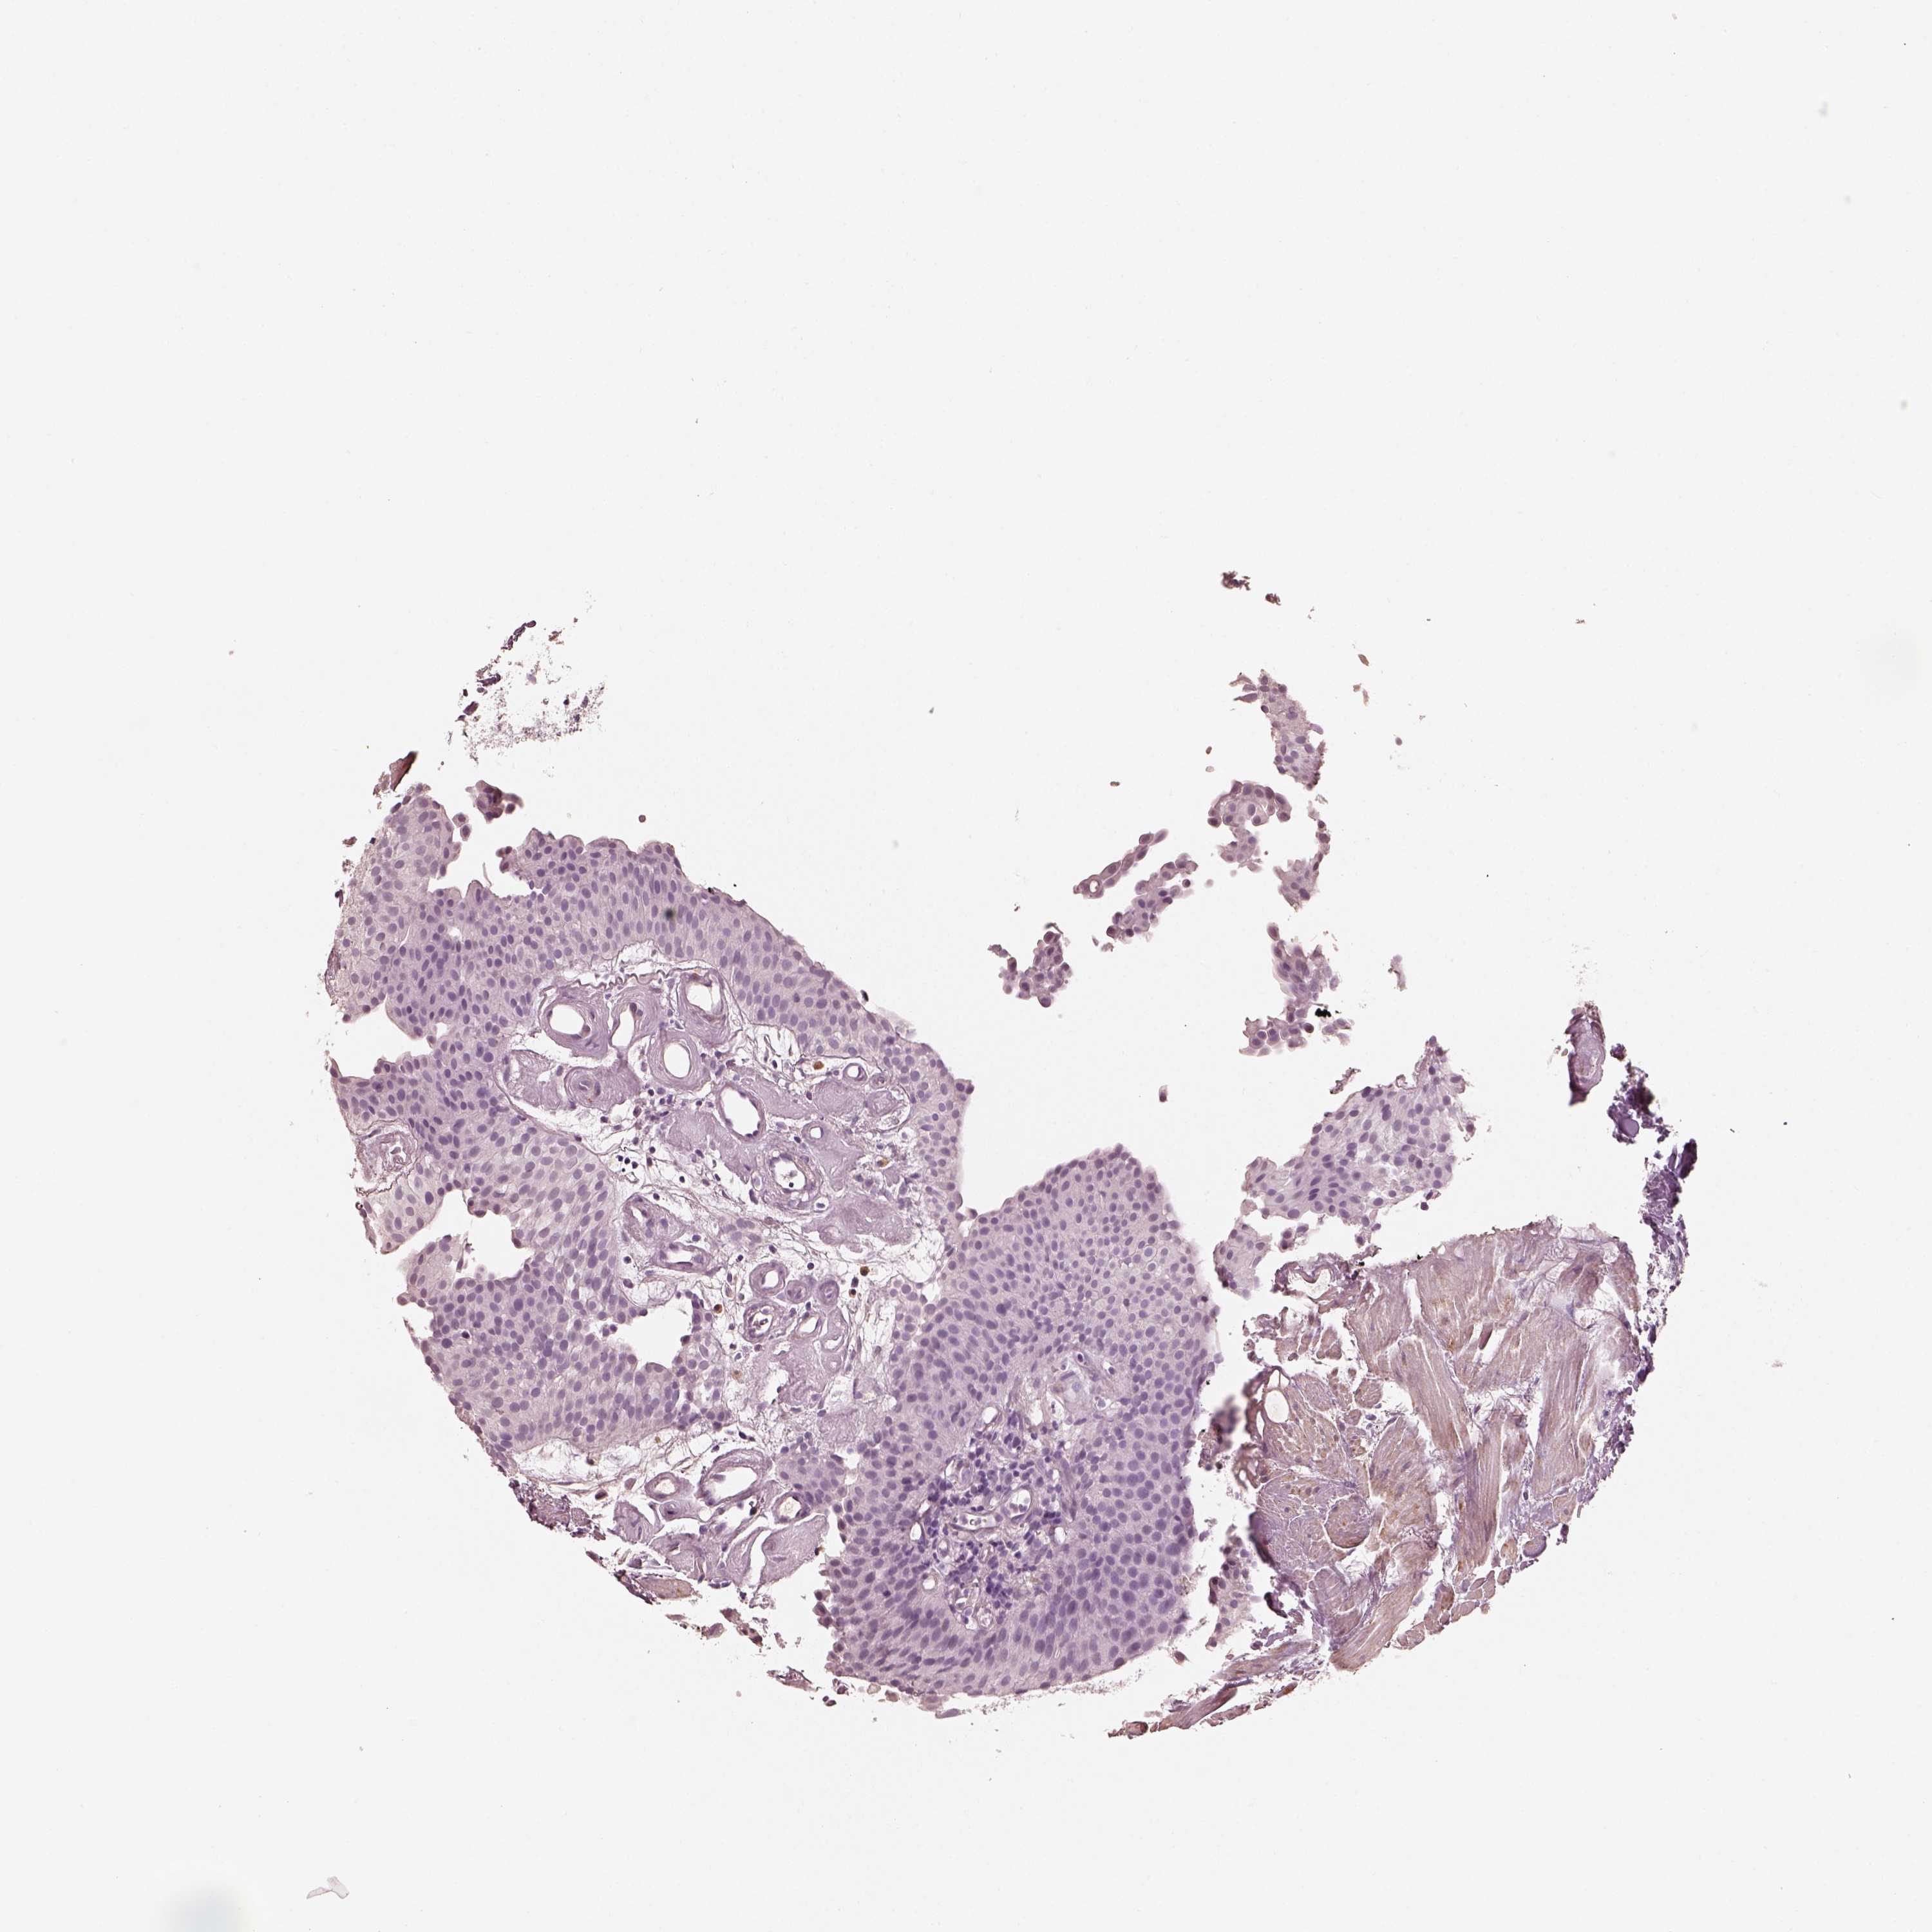

UROTHELIAL CANCER - Protein expressioni

A mouse-over function shows sample information and annotation data. Click on an image to view it in a full screen mode. Samples can be filtered based on level of antibody staining by selecting one or several of the following categories: high, medium, low and not detected. The assay and annotation is described here.

Note that samples used for immunohistochemistry by the Human Protein Atlas do not correspond to samples in the TCGA dataset.

Antibody stainingi

Antibody staining in the annotated cell types in the current human tissue is reported as not detected, low, medium, or high, based on conventional immunohistochemistry profiling in selected tissues. This score is based on the combination of the staining intensity and fraction of stained cells.

Each image is clickable and will lead to virtual microscopy that enables deeper exploration of all samples and also displays staining intensity scores, fraction scores and subcellular localization as well as patient and tissue information for each sample.

Antibody HPA059546

Staining

High

Medium

Low

Not detected

Intensity

Strong

Moderate

Weak

Negative

Quantity

>75%

75%-25%

<25%

None

Location

Nuclear

Cytoplasmic/membranous

Cytoplasmic/membranous,nuclear

Urothelial carcinoma, High grade

Urothelial carcinoma, Low grade